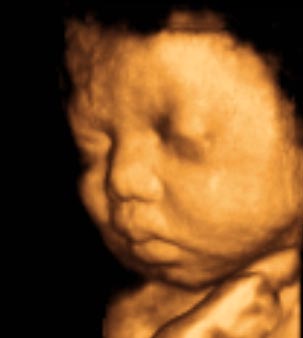

• 香港结构超声波照片

香港结构超声波照片

结构性超声波, 四维 香港, 四维结构性超声波 结构性超声波, 四维 结构性超声波, 四维 香港, 四维结构性超声波 结构性超声波, 四维 香港, 四维结构性超声波 结构性超声波, 四维 结构性超声波, 四维 结构性超声波, 四维 香港, 四维结构性超声波 结构性超声波, 四维 香港, 四维结构性超声波 结构性超声波, 四维 结构性超声波, 四维